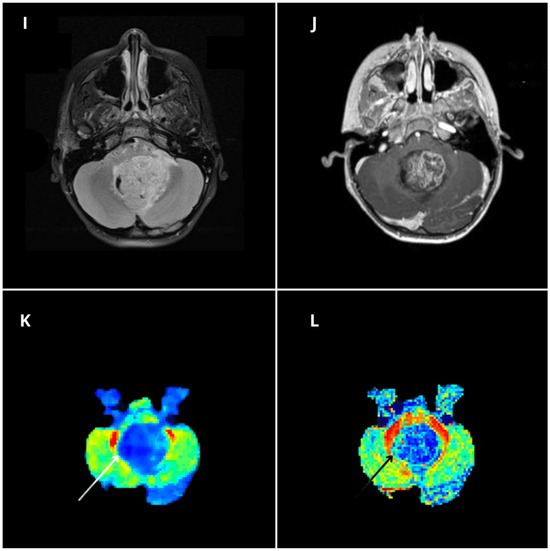

Figure 5.

Diffusion kurtosis imaging-based findings to discriminate between pediatric posterior fossa tumors. MRI images are of a 7-year-old girl affected by a WHO grade I pilocytic astrocytoma (A–D), a 10-year-old boy affected by medulloblastoma (E–H), and an 8-year-old boy affected by a WHO grade II ependymoma (I–L). Native MPRAGE T1 post-contrast images (B,F,J) show three contrast-enhancing posterior fossa tumors located within the fourth ventricle, presenting a variable proportion of solid and cystic components. Qualitative evaluation of the mean kurtosis (MK) color maps (C,G,K) reveals significant differences between the lesions, with the pilocytic astrocytoma (PA) presenting relatively lower MK values ((C), white arrow), the ependymoma (EP) presenting intermediate MK values ((K), white arrow), and the medulloblastoma (MB) presenting high MK values compared with the other two lesions ((G), white arrow). Whole tumor labeling (green label) on the co-registered contrast-enhanced MPRAGE (B,F,J) and MK maps (C,G,K) yielded quantitative whole-tumor MK values of 0.40, 0.55, and 1.04, for PA, EP and MB respectively.

Post hoc Benjamini–Hochberg-corrected t tests showed all DKI metrics were significantly different between medulloblastoma and pilocytic astrocytoma (p < 0.001 for all metrics, asterisk). Moreover, RK, MK, and AK were significantly different between medulloblastoma and ependymoma (p < 0.012, p < 0.001, and p < 0.001, respectively, triangle), and AK, FA, and MD were significantly different between pilocytic astrocytoma and ependymoma (p < 0.048, p < 0.001, and p < 0.004, star, respectively). Thus, different specific DKI-derived diffusion metrics were useful in discriminating among specific tumor subtypes.